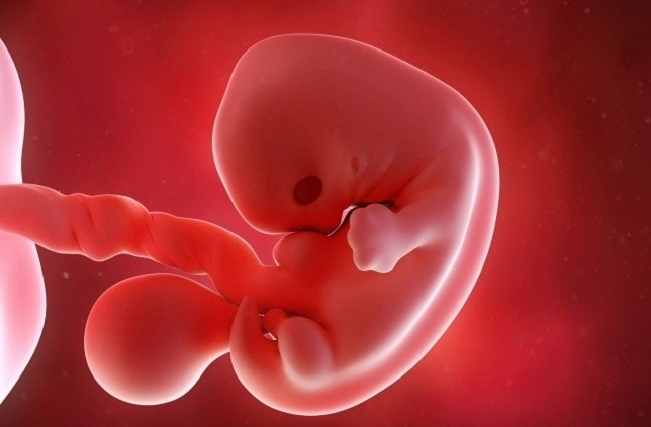

Khi mẹ đi khám thai và siêu âm trong giai đoạn thai nhi 7 tuần tuổi, hình ảnh siêu âm thai 7 tuần tuổi cho thấy bé bắt đầu phát triển và hình thành các bộ phận cơ thể như sau:

Tóm lại, khi thai 7 tuần tuổi là giai đoạn thai nhi bắt đầu phát triển rõ rệt và mẹ cần đi khám thai và siêu âm tại thời điểm này. Hình ảnh siêu âm thai 7 tuần tuổi cho biết sự hình thành của các cơ quan trong cơ thể thai nhi, nghe nhịp tim thai nếu có cũng như phát hiện những dấu hiệu bất thường ở mẹ và bé.